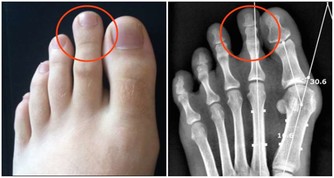

5 、降低你的血壓

超重是高血壓的主要危險因素,你看大腹便便者大部分都是高血壓的潛在客戶,不及時減重,早晚有一天會患上高血壓。已經有相關研究證實,體重每升高1KG,血壓值就會升高1mmHg,用BMI的公式=體重(kg)/身高(m)²,正常值應該在18.5-23.9之間,你看看自己的體重是否在正常範圍內,比正常值高了多少公斤,把這些加到你的血壓上,想想就覺得很可怕。